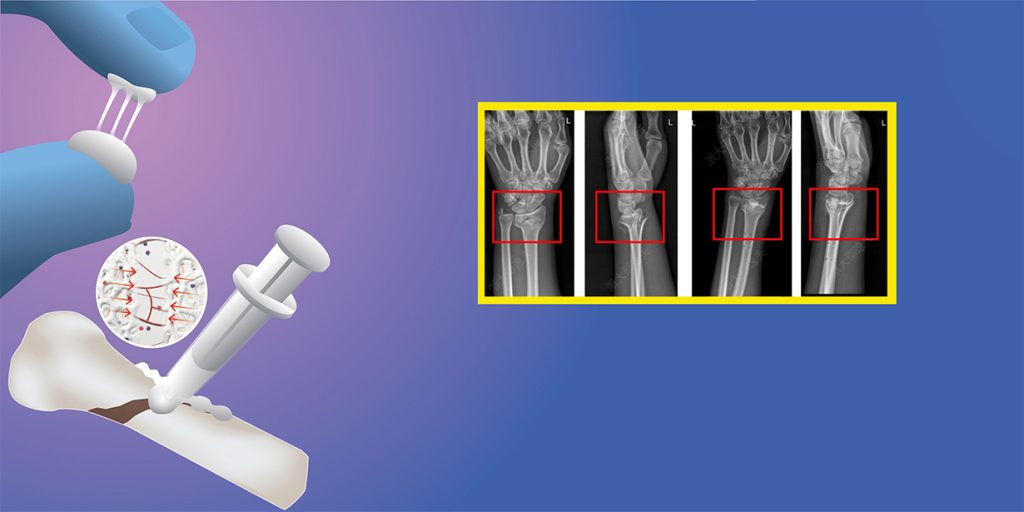

चिनियाँ वैज्ञानिकहरुले बोन ०२ नामक उक्त जैविक पदार्थको विकास गरेका हुन्, जो हड्डीहरुलाई जोड्नका लागि प्रयोग गरिन्छ । यो सामुद्रिक सिपीबाट प्रेरित छ, जुन समुद्रमा बलियो सँग टाँसिएको हुन्छ ।

सोही विचारको आधारमा उनले उक्त बोन ग्लू बनाए । उक्त ग्लूले २ सय केजीभन्दा धेरै वजन भएको वस्तुलाई समेत टाँस्ने क्षमता राख्दछ । सर्जरीका क्रममा उक्त ग्लूलाई लगाउनाले भाँच्चिएका हड्डीहरु २–३ मिनेटमै जोडिन्छन् ।

चीनको वेन्झोउमा डाक्टर लिनको टोलीले यो ग्लूको विकास गरेका हुन् । उक्त ग्लूको परीक्षण डेढ सय भन्दा धेरै बिरामीमा गरिएको र त्यो सबै सुरक्षित र प्रभावकारी सावित भएको थियो ।